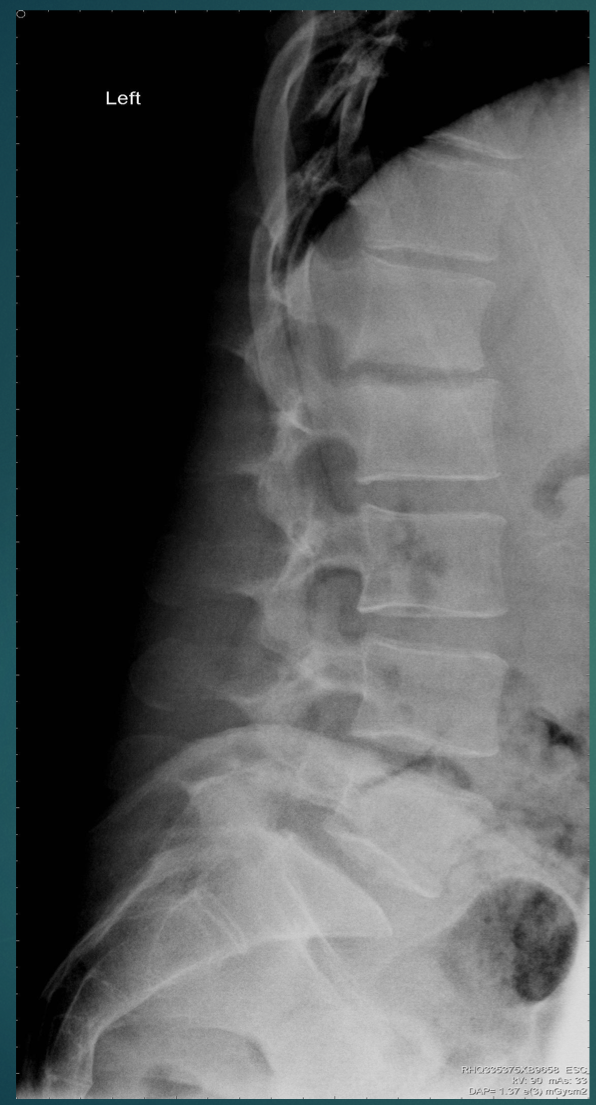

40 YO M. Several months of back pain.

Entire joint space gone

T12-L1 Disc is gone

• Think: Infectious discitis